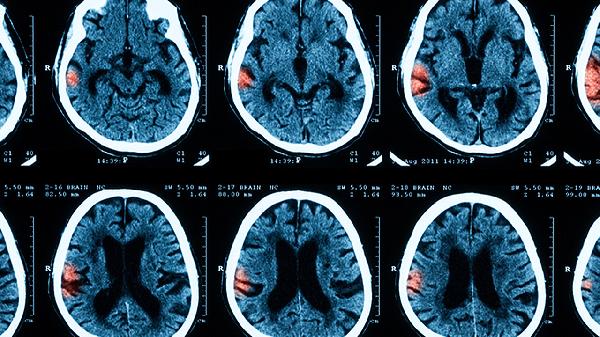

五岁宝宝出现这些症状要警惕脑膜炎

五岁儿童患脑膜炎时,常见的症状包括发烧、头痛、呕吐、颈部僵硬以及精神状态的变化。脑膜炎的发展过程通常分为几个阶段,早期可能表现得不太明显,随后逐渐出现神经系统体征、意识障碍、抽搐及全身性的并发症。